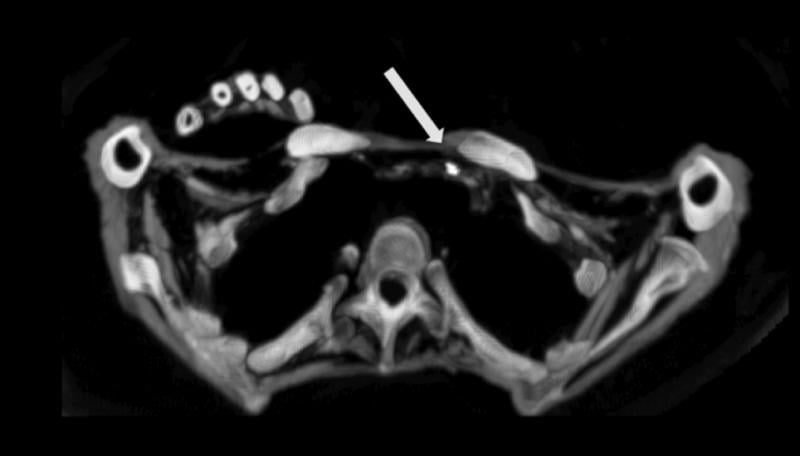

CT scan showing Egyptian mummy with calcified aortic bifurcation.

While the HORUS Study has previously reported atherosclerotic vascular calcifications on computed tomography (CT) scans in ancient Egyptians, the HORUS team’s new study was to compare patterns and demographic characteristics of this disease among Egyptians from both ancient and modern eras.[1] The scans at the Museum of Egyptian Antiquities were performed using a Siemens Somatom Emotion 16-slice CT system. The authors compared the presence and extent of vascular calcifications from whole-body CT scans performed on 178 modern Egyptians from Cairo undergoing positron emission tomography (PET)/CT for cancer staging to CT scans of 76 Egyptian mummies (3100 BC to 364 AD). Patients undergoing cancer staging were selected for the study because these scans had already been completed for this group of patients as part of their cancer care.

The mean age of the modern Egyptian group was 52 years (range 14 to 84) versus estimated age at death of ancient Egyptian mummies 36 years (range 4 to 60). Vascular calcification (evidence of atherosclerosis) was detected in 108 of 178 (61%) of modern patients versus 26 of 76 (38%) of mummies, with vascular calcifications on CT strongly correlated to age in both groups. In addition, the severity of disease by number of involved arterial beds also correlated to age, and there was a very similar pattern between the two groups.